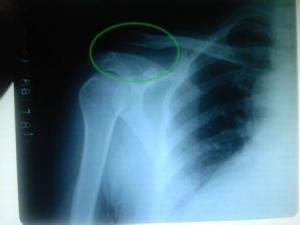

♥肩锁关节脱位

肩锁关节脱位并非少见,在肩部损伤中占4%~6%左右,手法复位后制动较为困难,因而手术率较高。